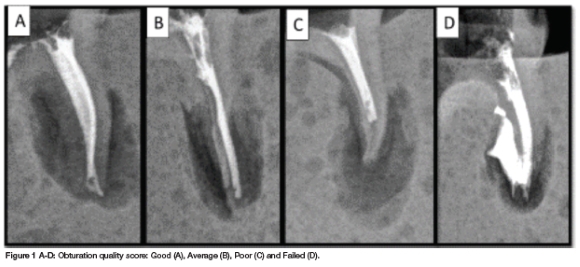

The presence of voids (Score 1-4) and the extent of fill (Grade A-D+) were combined to grade obturation quality (Table 1). Each tooth was graded as "good", "average", "poor" or "failed" (Figure 1).

The proportion of "good" obturation outcomes observed with the ProTaper Gold SX group (65%) was significantly higher than observed in the K-file group (25%, p = 0.025) but was similar to the proportion of "good" outcomes observed in the WaveOne Gold Medium group (55%, p = 0.748). The proportion of "average" obturation outcomes was similar across the three groups (Table 2). The proportion of "poor" obturation outcomes was significantly higher in the K-file group (40%) than that observed in the ProTaper Gold SX group (5%; p = 0.020). No other significant differences were observed (Table 2).

In this study, obturation quality was assessed. Three different preparation instrumentations were used to prepare root canals during pulpectomy treatment. The authors found that manual preparation resulted in more "poor" obturation outcomes than the outcomes observed using rotary files. These findings are similar to the results of several other studies.3,9,19,20 No significant differences in obturation quality were observed when comparing rotating or reciprocating files in the preparation of primary teeth.

1. The rotary ProTaper Gold SX file showed superior obturation quality followed by the reciprocating WaveOne Gold Medium file and then conventional ss K-files.

2. The K-file group resulted in the most "poor" and "average" outcomes.

3. There was no significant difference in "failed" outcomes between all three groups.